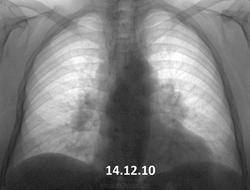

Вот такая динамика. В 2010 г. - в один день вдох-выдох- такая методика у предыдущего флюородоктора. Жалоб нет (кроме сердечных). Согласно КТ ОГК от декабря 2013 - лимфоаденопатия (как говорится - ни вашим, ни нашим). Вроде уже обращено внимание, пациент(ка) это ощутил. Успокоиться?

Картина одинаковая. Увеличение л/узлов средостения и лёгких. Хоть с каким диагнозом наблюдается. Сердечные проблемы здесь ни при чём, они только в ЗАГСе.

Динамики вроде нет.Похоже на саркоидоз.

Есть конечно, тот лимфоузел побольше стал. Диагноз однозначно нужно верифицировать.